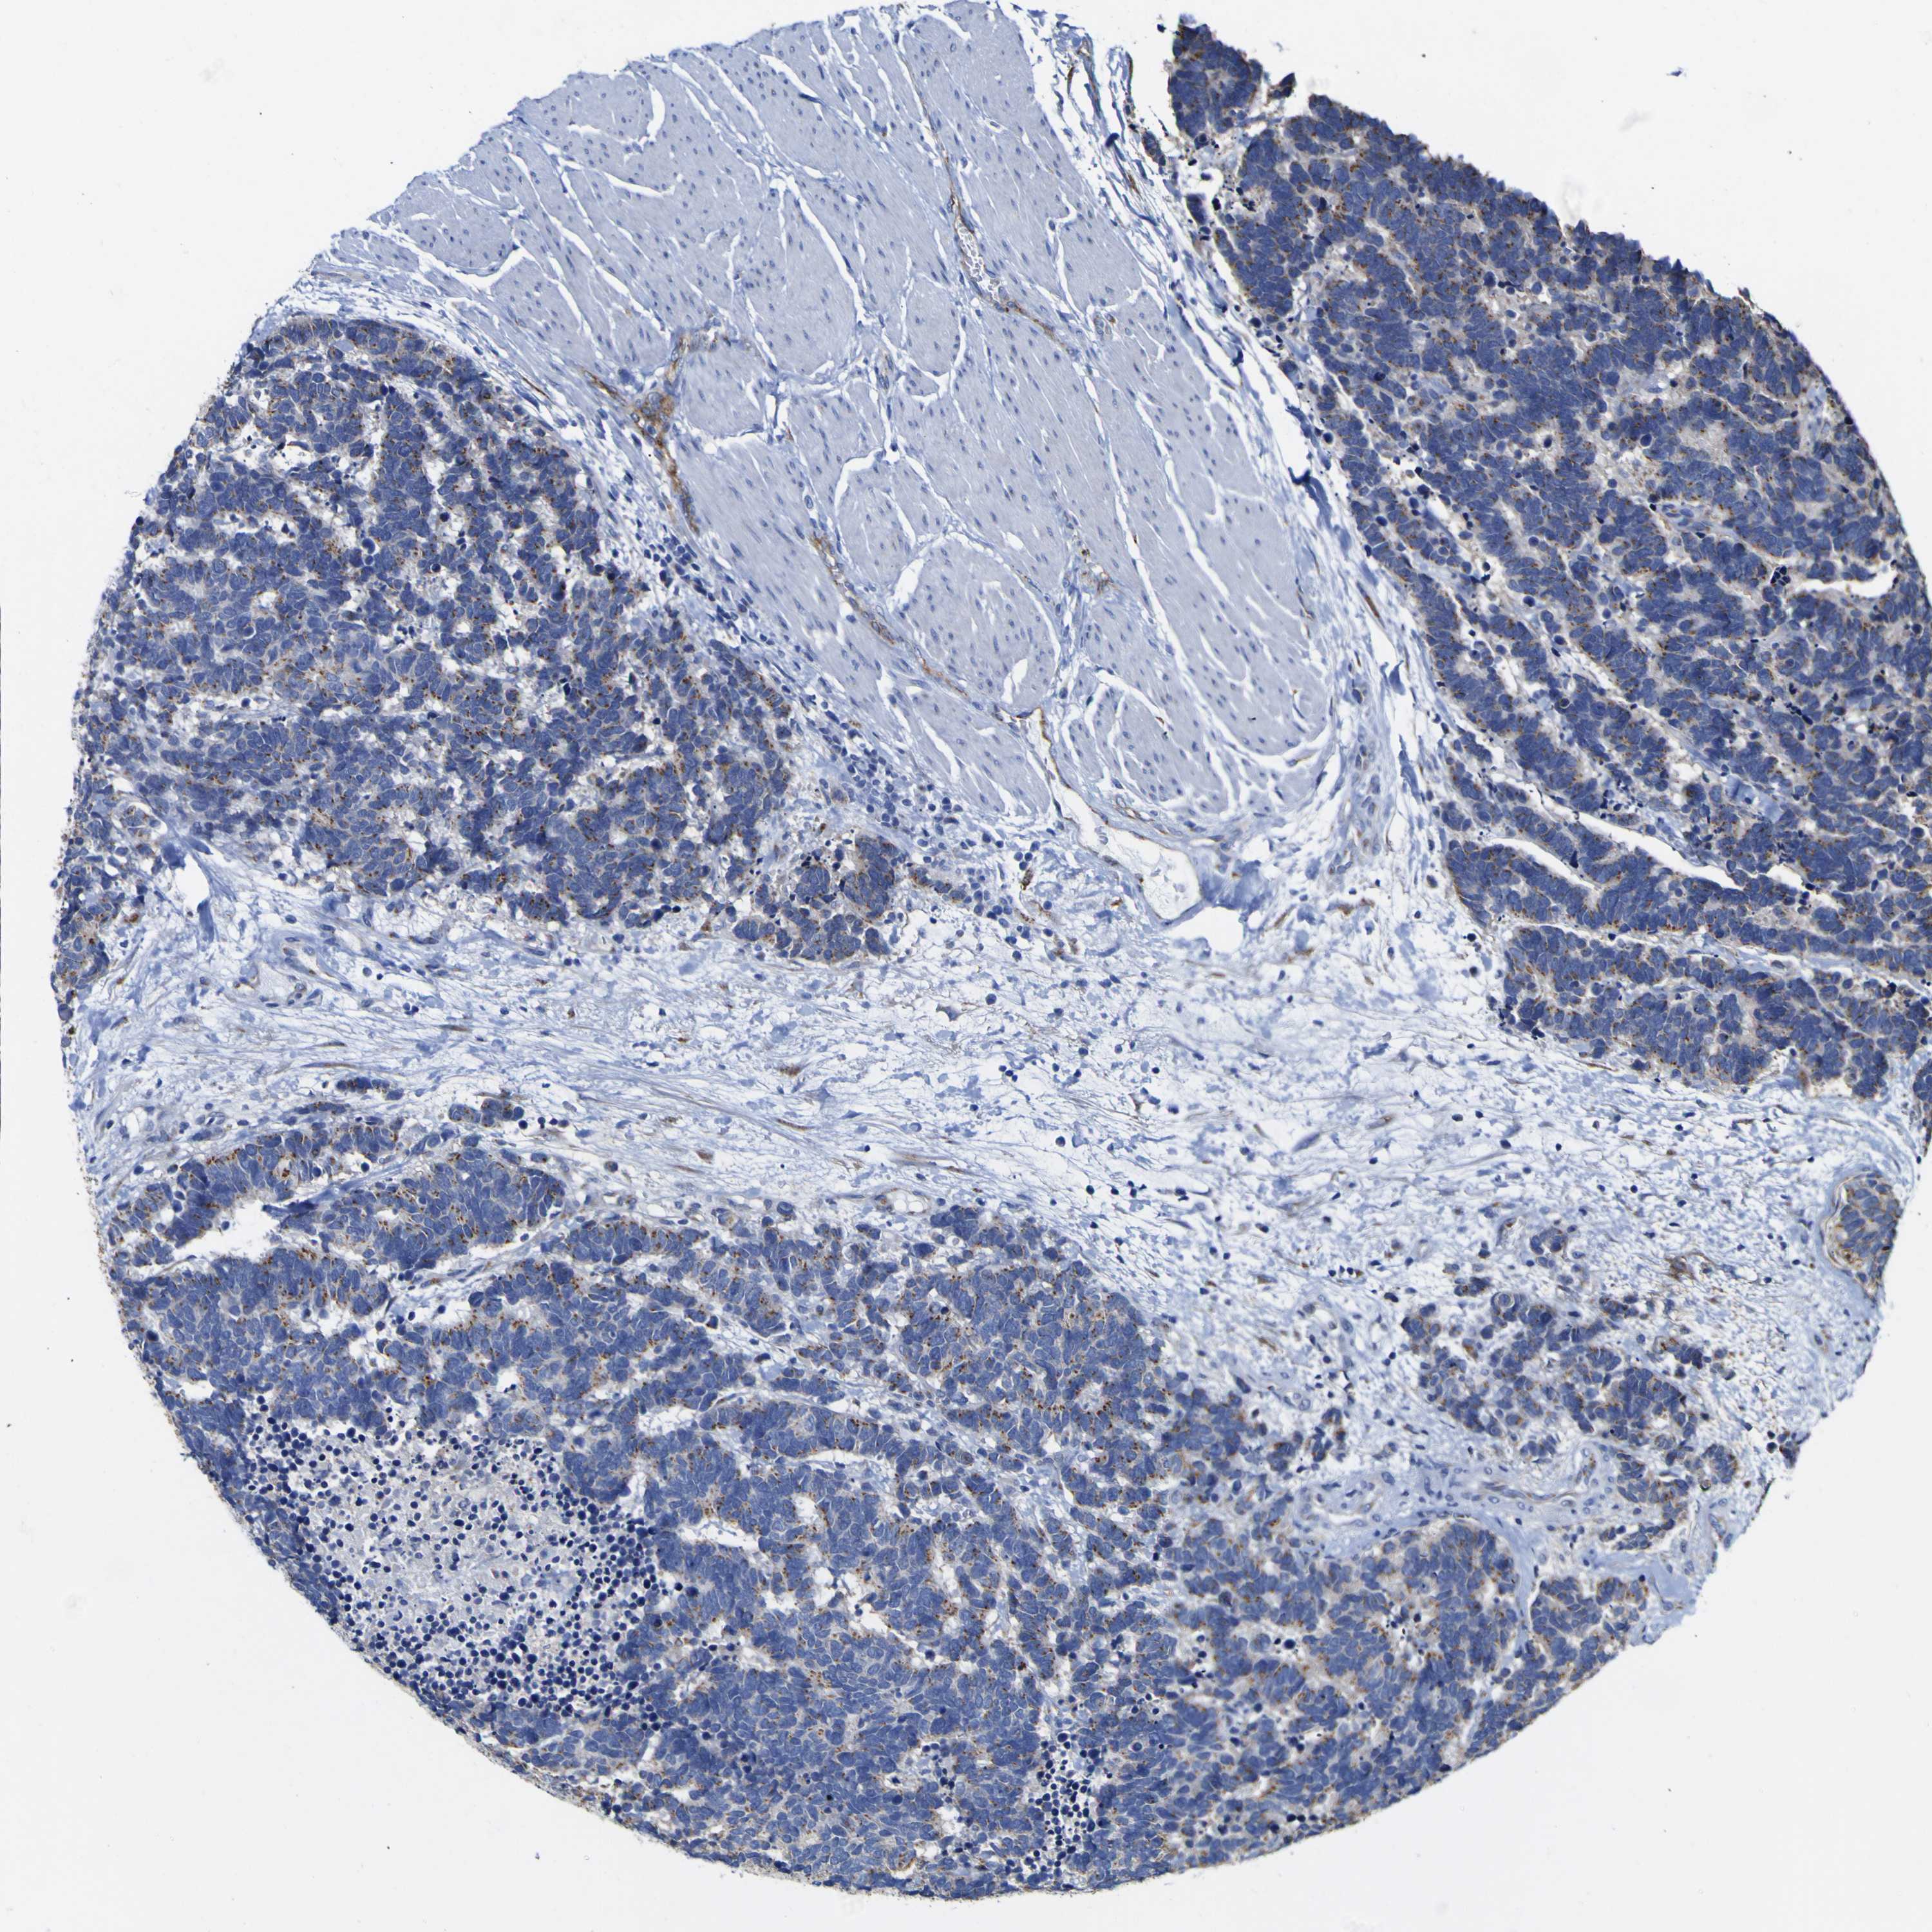

CARCINOID - Protein expressioni

A mouse-over function shows sample information and annotation data. Click on an image to view it in a full screen mode. Samples can be filtered based on level of antibody staining by selecting one or several of the following categories: high, medium, low and not detected. The assay and annotation is described here.

Each image is clickable and will lead to virtual microscopy that enables deeper exploration of all samples and also displays staining intensity scores, fraction scores and subcellular localization as well as patient and tissue information for each sample.

Antibody HPA010638

Staining

High

Medium

Low

Not detected

Intensity

Strong

Moderate

Weak

Negative

Quantity

>75%

75%-25%

<25%

None

Location

Nuclear

Cytoplasmic/membranous

Cytoplasmic/membranous,nuclear

Carcinoid, malignant, NOS

Carcinoma, NOS